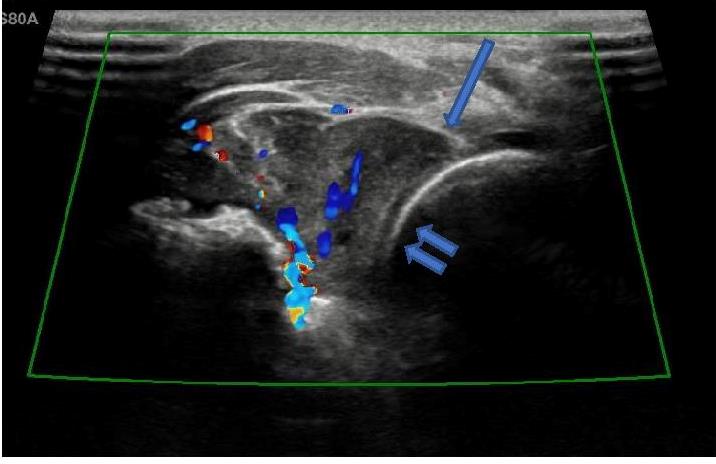

![]() |

Image D : Transverse image of dorsal proximal forearm, demonstrates vascularity of tumour. Arrow demonstrates tumour abutting radial head of proximal right radius (double arrow). |